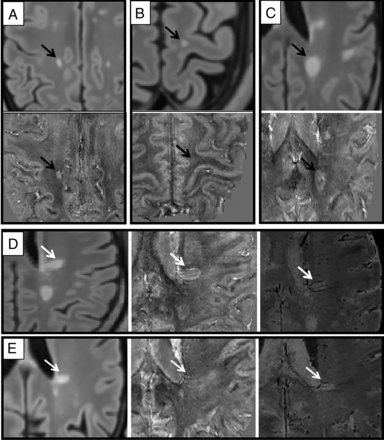

The QSM signal was used to classify WM lesions as hyperintense versus nonhyperintense. The latter includes both isointense lesions and hypointense lesions on QSM (ISO-HYPO), which showed a susceptibility not greater than that of surrounding normal-appearing WM. Hyperintense lesions, which showed higher susceptibility than the surrounding normal-appearing WM, were subsequently divided into 2 subgroups, according to their hyperintensity pattern: 1) PRLs, characterized by the presence of a hyperintense rim with respect to the center; and 2) hyperintense lesions (HYPER), characterized by a diffuse (either homogeneous or inhomogeneous) distribution of hyperintensity within the whole lesion. To better visualize veins, which are a potential confound for lesion classification due to their hyperintense appearance in QSM, we visually inspected SMWI to exclude the presence of blood vessels in QSM-hyperintense lesions. Lesions in which the confounding effect of blood vessels was not ruled out by SMWI inspection were excluded from further analyses. Figures 1 and 2 summarize our MS lesion classification approach.

Examples of different MS lesion phenotypes. A, B, and C, MS lesions (black arrow) on FLAIR (upper image) and on QSM (lower image) classified, respectively, in HYPER, ISO-HYPO, and PRLs groups. D and E, MS lesions (white arrows) on FLAIR (left), QSM (center), and SMWI (right), which were relocated, respectively, from PRLs to HYPER and from HYPER to ISO-HYPO groups; particularly in D, the hyperintense rim on QSM was determined to be composed of 2 veins (visible as hypointense signal in SMWI). E, The hyperintensity on QSM located at the center of the lesion was a central vein, as shown on SMWI.